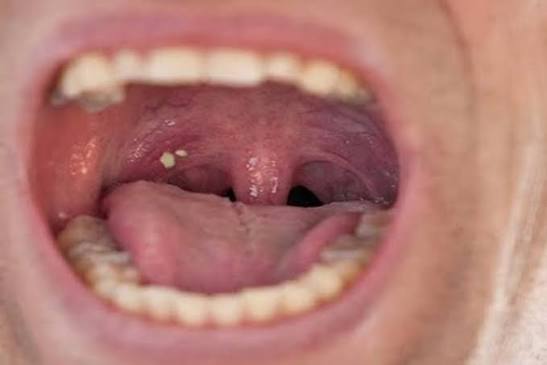

أوضح الخبراء أن هذه الحصوات، المعروفة طبيًا باسم tonsilloliths، تظهر غالبًا على شكل حبيبات بيضاء أو صفراء صغيرة داخل اللوزتين، وقد تكون واحدة أو عدة حصوات بأحجام مختلفة.

بحسب المتخصصين، تتكون حصوات اللوزتين عندما تتجمع بقايا الطعام والخلايا الميتة والبكتيريا داخل التجاويف الصغيرة الموجودة في اللوزتين، والمعروفة باسم "الشقوق اللوزية". ومع مرور الوقت تتصلب هذه المواد وتتحول إلى كتل صغيرة تشبه الحصى.